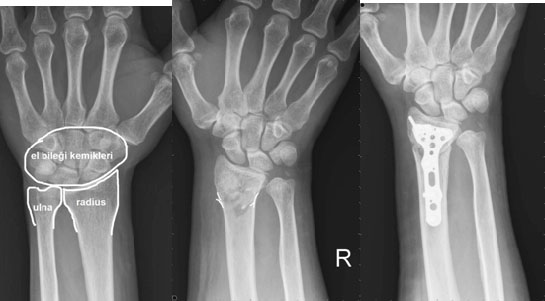

Bu tür yaralanmalar, genellikle ani ve beklenmedik durumlar sonucunda meydana gelir. Yaralanmanın ciddiyeti, kesik alanının derinliğine, kanamanın miktarına ve sinir veya tendonların etkilenip etkilenmediğine göre değişiklik gösterir. Kesilmiş Bilek Tedavi Aşamaları Kesilmiş bilek tedavisi, genellikle üç ana aşamadan oluşur: acil müdahale, cerrahi onarım ve rehabilitasyon.

Komplikasyonlar Kesilmiş bilek tedavisinde bazı komplikasyonlar ortaya çıkabilir. Bu komplikasyonlar arasında: